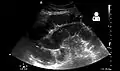

Upright abdominal X-ray demonstrating a small bowel obstruction. Note multiple air fluid levels.